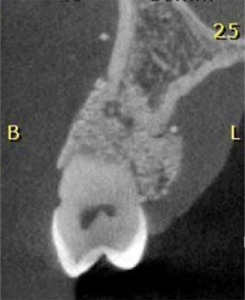

2, 3 e 4 | Diferentes planos tomográficos, evidenciando a real extensão da lesão.

18, 19 e 20 | Diferentes planos tomográficos, evidenciando o preenchimento do defeito com biomaterial e a regeneração óssea.